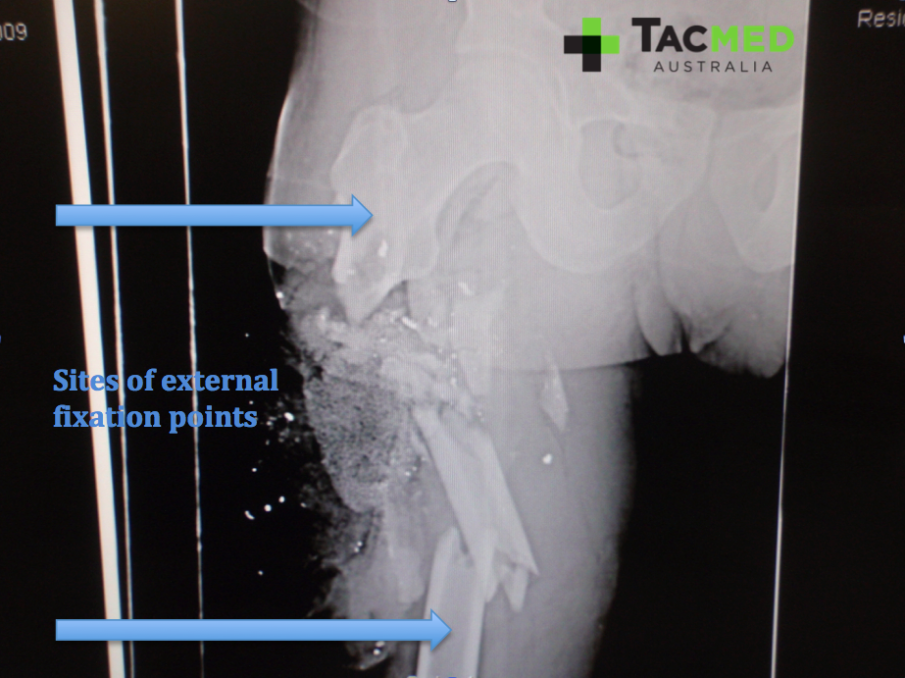

As with any limb injury, a high priority was to assess for blood flow distal to the wound in order to ascertain if the major blood vessels had been damaged. Remarkably, the casualty had normal blood flow to his feet, implying that the femoral artery was intact. Next came an X-ray to have a look at the underlying bone structures. The casualty had minimal movement in the leg at time of review, and we expected him to have a fracture of his femur underlying the injury. The following images of the X-ray highlight the main features, including the shattered femur from where the bullet struck, the bullet fragments from where the projectile had disintegrated on impact, and the granular material of the ACS.

Once we were comfortable that the casualty was medically stable enough to go to surgery, he was wheeled through to the operating theatre where we prepared him for his initial wound surgery. The priorities in the FST setting were to perform a procedure known as a debridement, which is the removal of any dead tissue that is likely to cause infection if left in place, as well as stabilization of any fractures. For the latter, a technique know as external fixation is used frequently in the context of war wounds. In external fixation, a series of surgical screws are drilled into the good bone above and below the fractured area, and then an external frame is constructed to stabilize the fracture.

Once the pins had been appropriately placed above and below the fracture site, the femur was pulled back out to its appropriate length and stabilized with external rods bolted onto the screws in the bones. The various pieces of shattered femur that can be seen in the X-ray images were all put back in their rightful place with the hope that they would heal back together as any other fractured bone does.